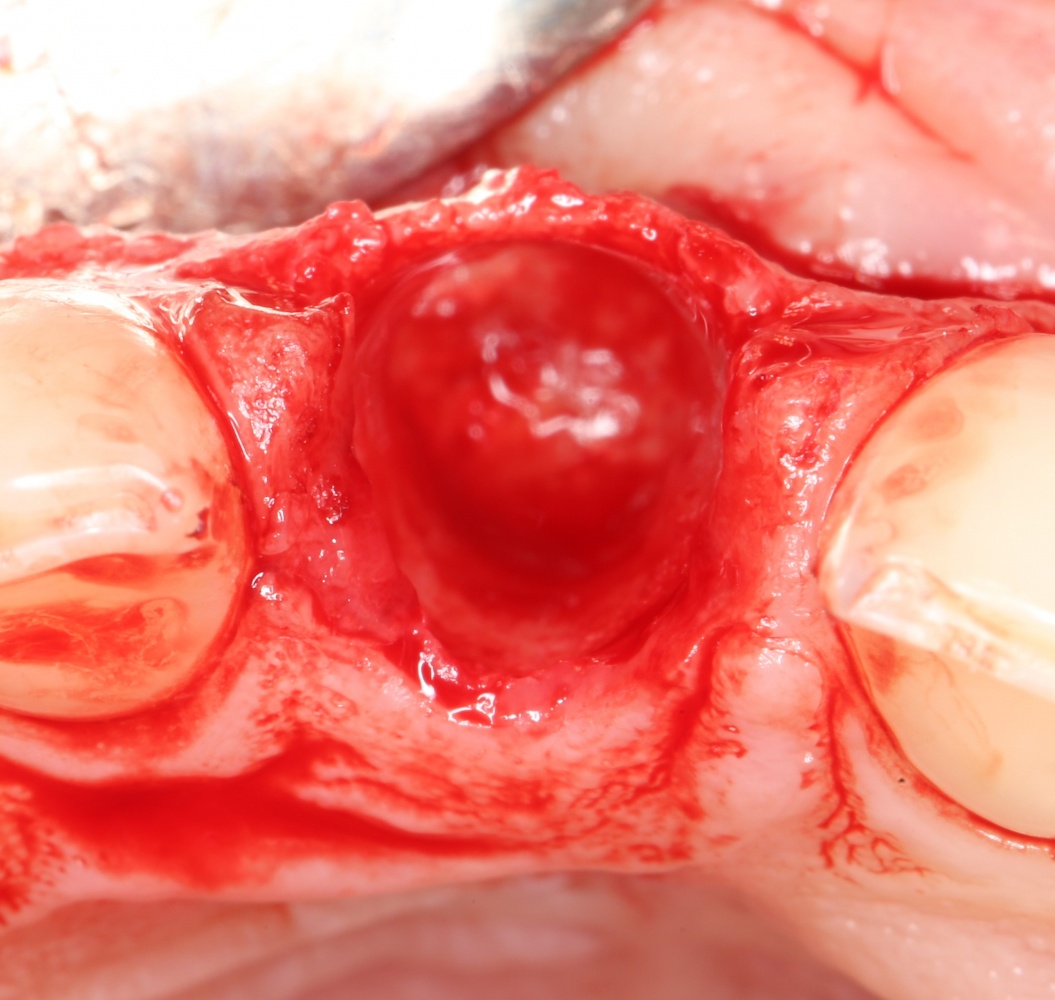

После удаления зуба и сопутствующей гранулемы, остается большая по размеру лунка с тонкой и поврежденной воспалительным процессом вестибулярной стенкой:

Первым делом, необходимо определиться с подготовкой лунки под имплантат. Проверить правильность позиционирования лунки можно с помощью аналогов имплантов, входящих в комплект XiVE Dentsply Implants:

Напомню, что при правильном позиционировании импланта в области фронтальных зубов, он прилегает к небной стенке лунки, а его ось выходит на небную поверхность будущей коронки. В крайнем случае, на режущий край.

Имплантат по объему всегда меньше, чем сам зуб:

Поэтому у нас возникает вопрос заполнения «пустого» пространства между вестибулярной стенкой лунки и поверхностью импланта. И, как ни странно, с Bio-Oss Collagen это удобнее сделать до установки имплантата.